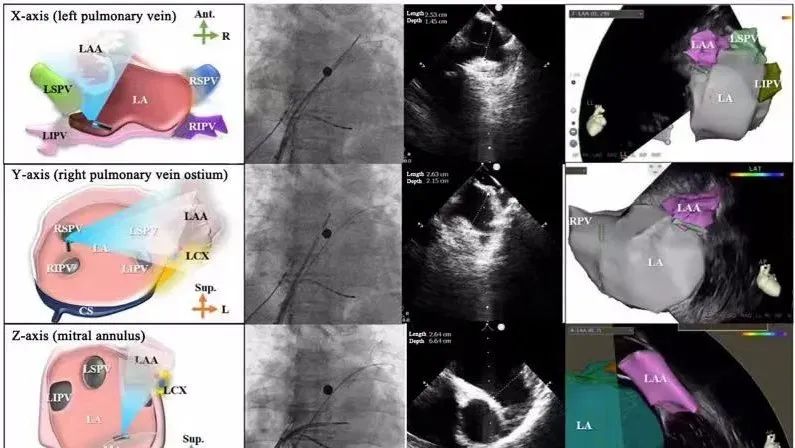

一種與心導管檢查相結合的超聲心動圖診斷新興技術,通過將超聲探頭置于心腔內(nèi)部,發(fā)射并接收超聲信號,來精確獲取心臟解剖結構、心臟血流動力學等信息的實時成像。與其他影像技術相比,ICE技術具有操作簡單、無輻射、安全性高、手術效率高、實用等優(yōu)勢,ICE在很大程度上有望取代經(jīng)食道超聲心動圖(TEE),成為電生理和結構性心臟病領域的理想成像方式。

心腔內(nèi)超聲(ICE)技術壁壘極高,國內(nèi)主要廠商核心部件仍舊為進口,集成了超聲和圖像處理最前端技術,包括超聲探頭、線纜、軟件成像算法等,是當前內(nèi)窺超聲方向最具挑戰(zhàn)的領域。ICE的應用經(jīng)歷了2D平面成像、3D三維立體成像、以及4D的實時三維立體成像階段。